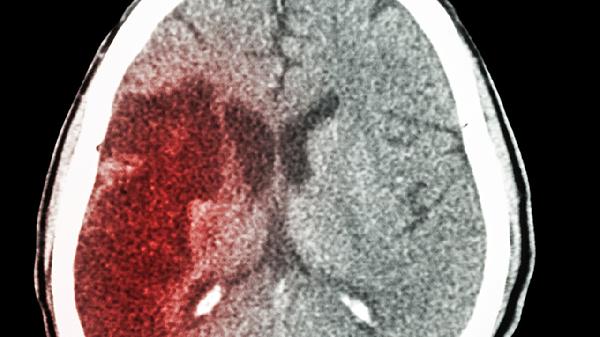

突然出现的视物模糊、说话不清、肢体麻木,可能是斑块脱落的信号,要立即就医。